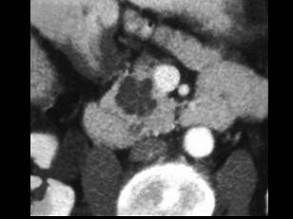

患者,女,57岁,上腹部隐痛半年余,CT片,最可能的诊断是 ( )A、胰腺囊腺瘤B、胰岛细胞瘤C、胰腺脓肿D、胰腺假性囊肿E、胰腺癌

问题 患者,女,57岁,上腹部隐痛半年余,CT片,最可能的诊断是 ( )

选项 A、胰腺囊腺瘤 B、胰岛细胞瘤 C、胰腺脓肿 D、胰腺假性囊肿 E、胰腺癌

答案 A